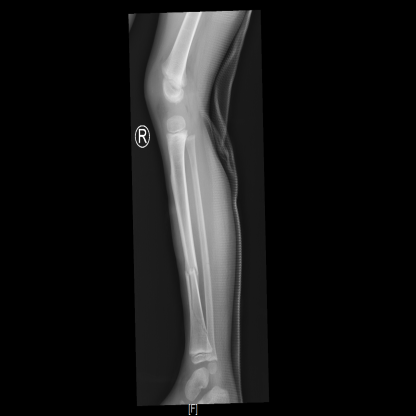

日前,小曹同学玩耍时不慎被小轿车撞伤,伤及右小腿,当时疼痛、肿胀伴活动受限,急就诊于当地医院,行X线示:右胫腓骨骨折,给予石膏外固定,建议手术治疗,家长为进一步诊治来到河北省儿童医院。

创伤外科(急诊外科)副主任崔硬铁接诊后,查体、阅片,小曹双上肢及左下肢未见异常,右小腿局部肿胀,压痛明显,可闻及骨擦音,可触及骨擦感,右膝、右踝关节活动受限,右足各趾活动可,右足背动脉搏动可触及,末稍血运及感觉良好,以“右胫腓骨骨折”收入创伤外科。

术后给予患儿儿童骨折优质护理,止血及消肿治疗,抬高患肢,注意观察患肢末梢血运。复查X线示:右侧胫腓骨可见外固定影,右胫骨下段可见金属内固定,断端对位对线可,周围未见明确骨痂形成。小曹病情平稳,向患儿家属交代病情及出院注意事项,现已顺利出院。